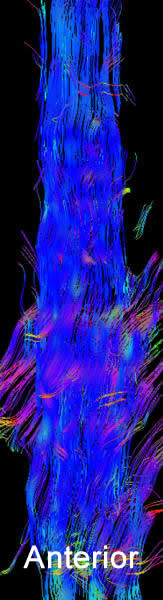

MRI of the dorsal spine with contrast and myelography and fibertraking and spectroscopy showing the recent lesions as seen in the below pictures with abscess formation.

MRI showing the new flare with abscess malformation and the old one

Fibertraking of the spinal cord at the lesion showing some scanty fibers ready for attack from behind (The middle picture)